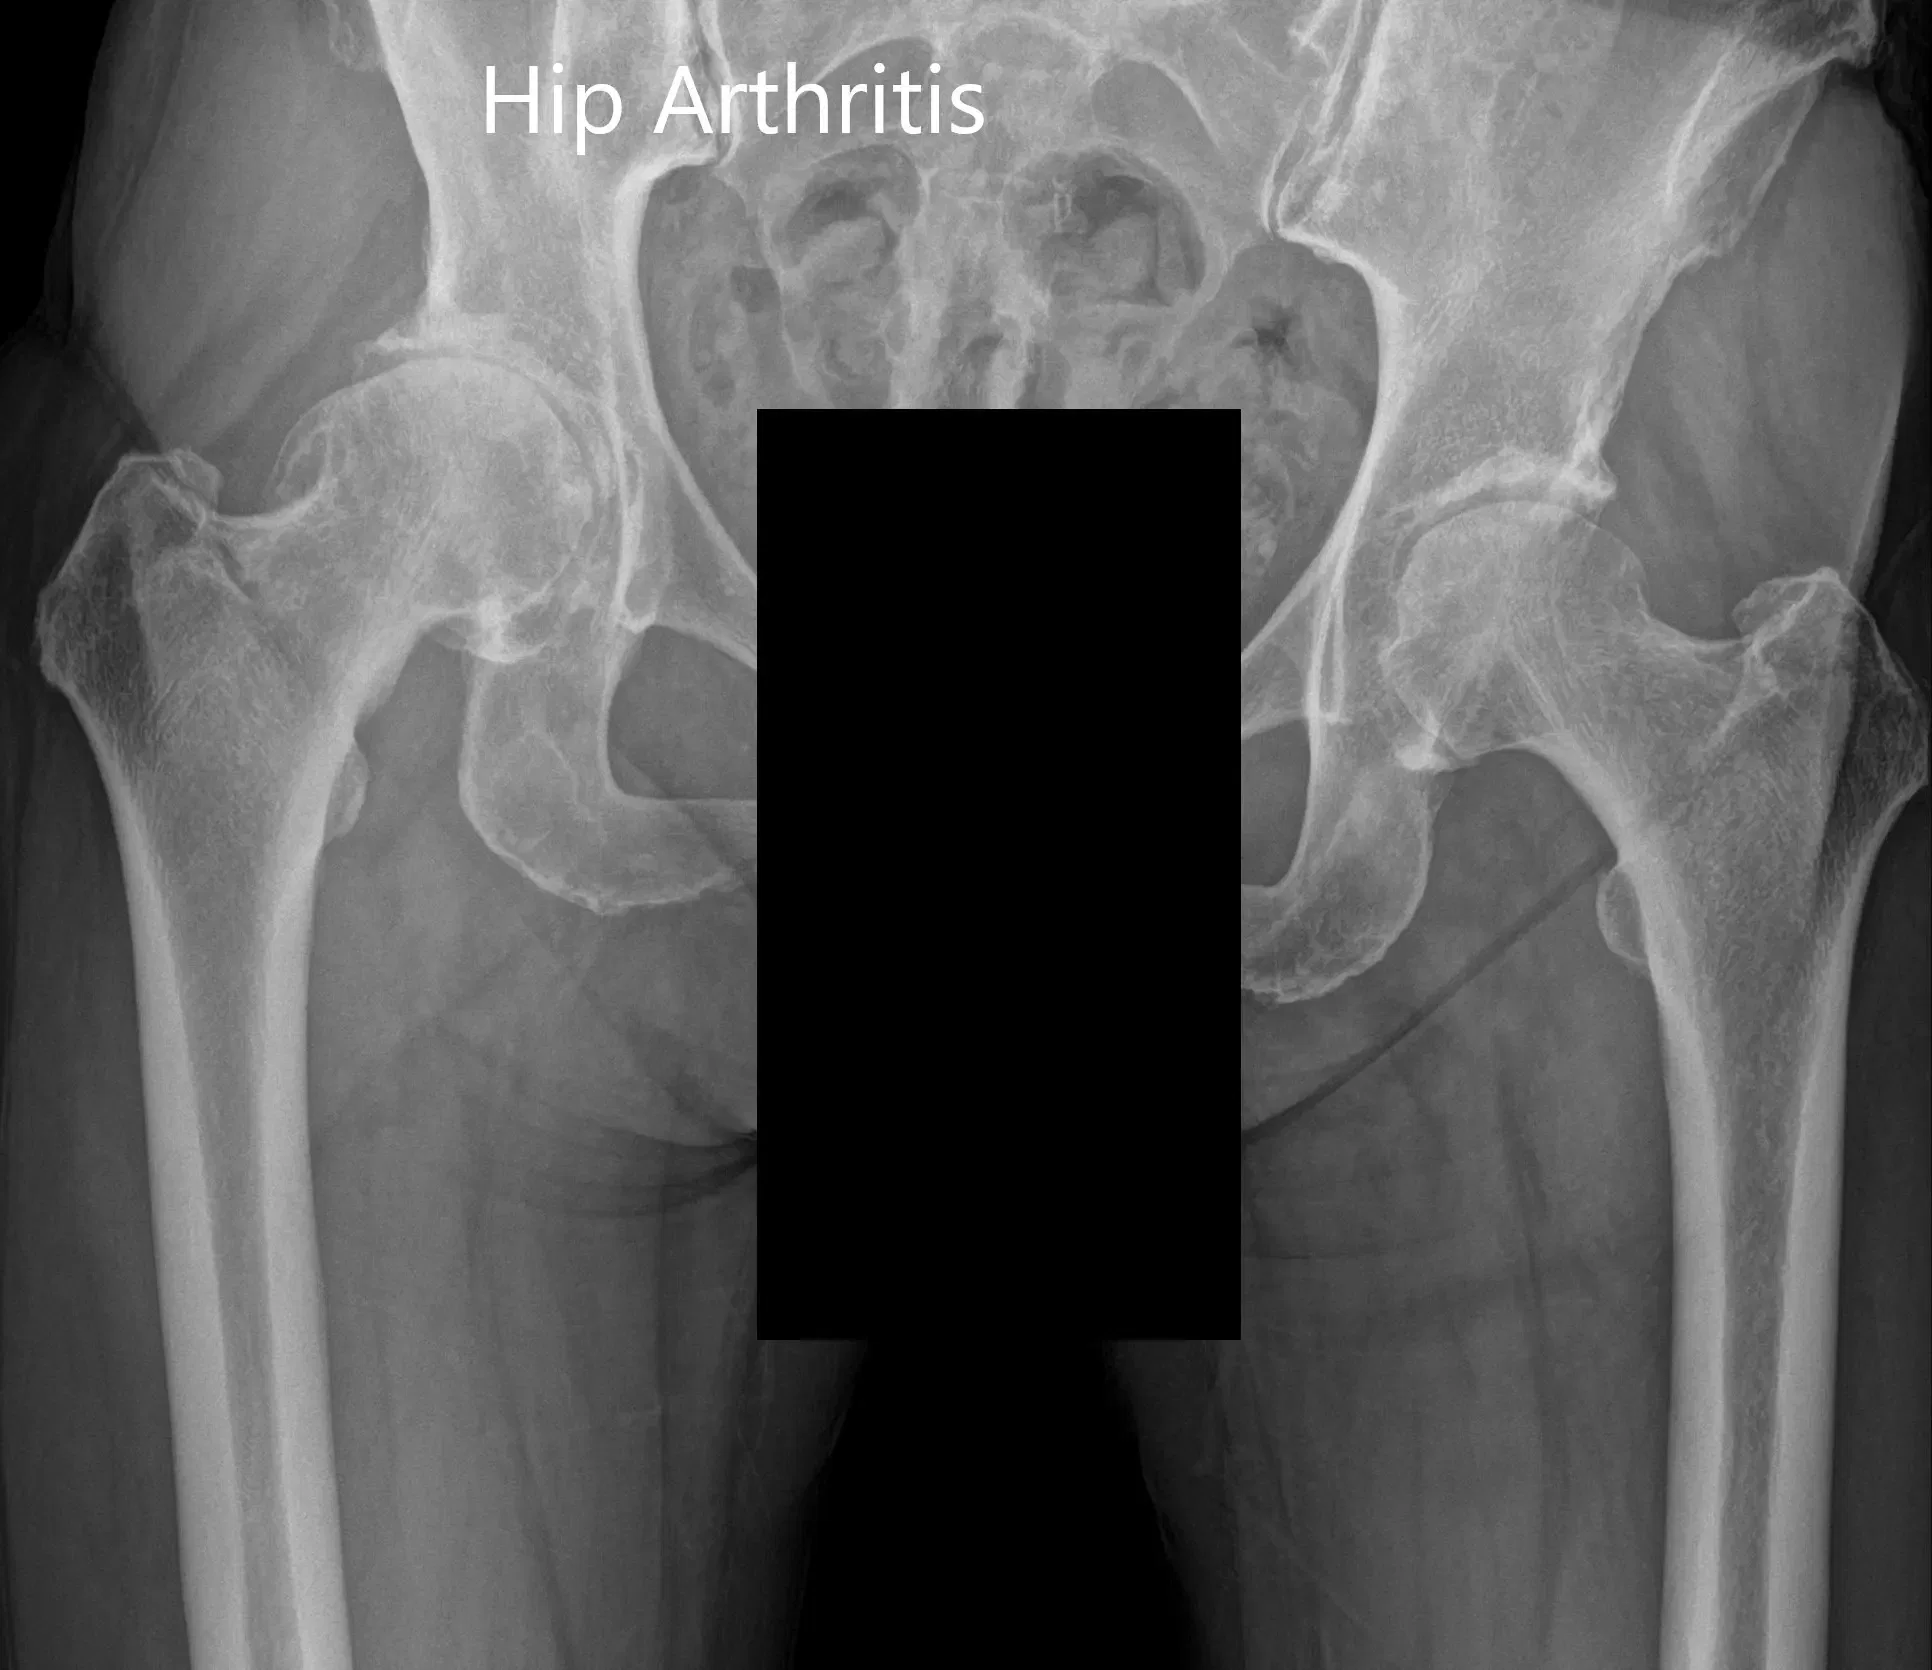

Las imágenes revelaron osteoartritis en la cadera derecha con reducción del espacio articular y osteófitos. Al paciente se le recomendó un reemplazo robótico total de cadera a la derecha. Los riesgos, beneficios y alternativas se discutieron extensamente con la paciente y ella estuvo de acuerdo con el plan.

Radiografía preoperatoria que muestra la vista AP de la pelvis con ambas caderas.